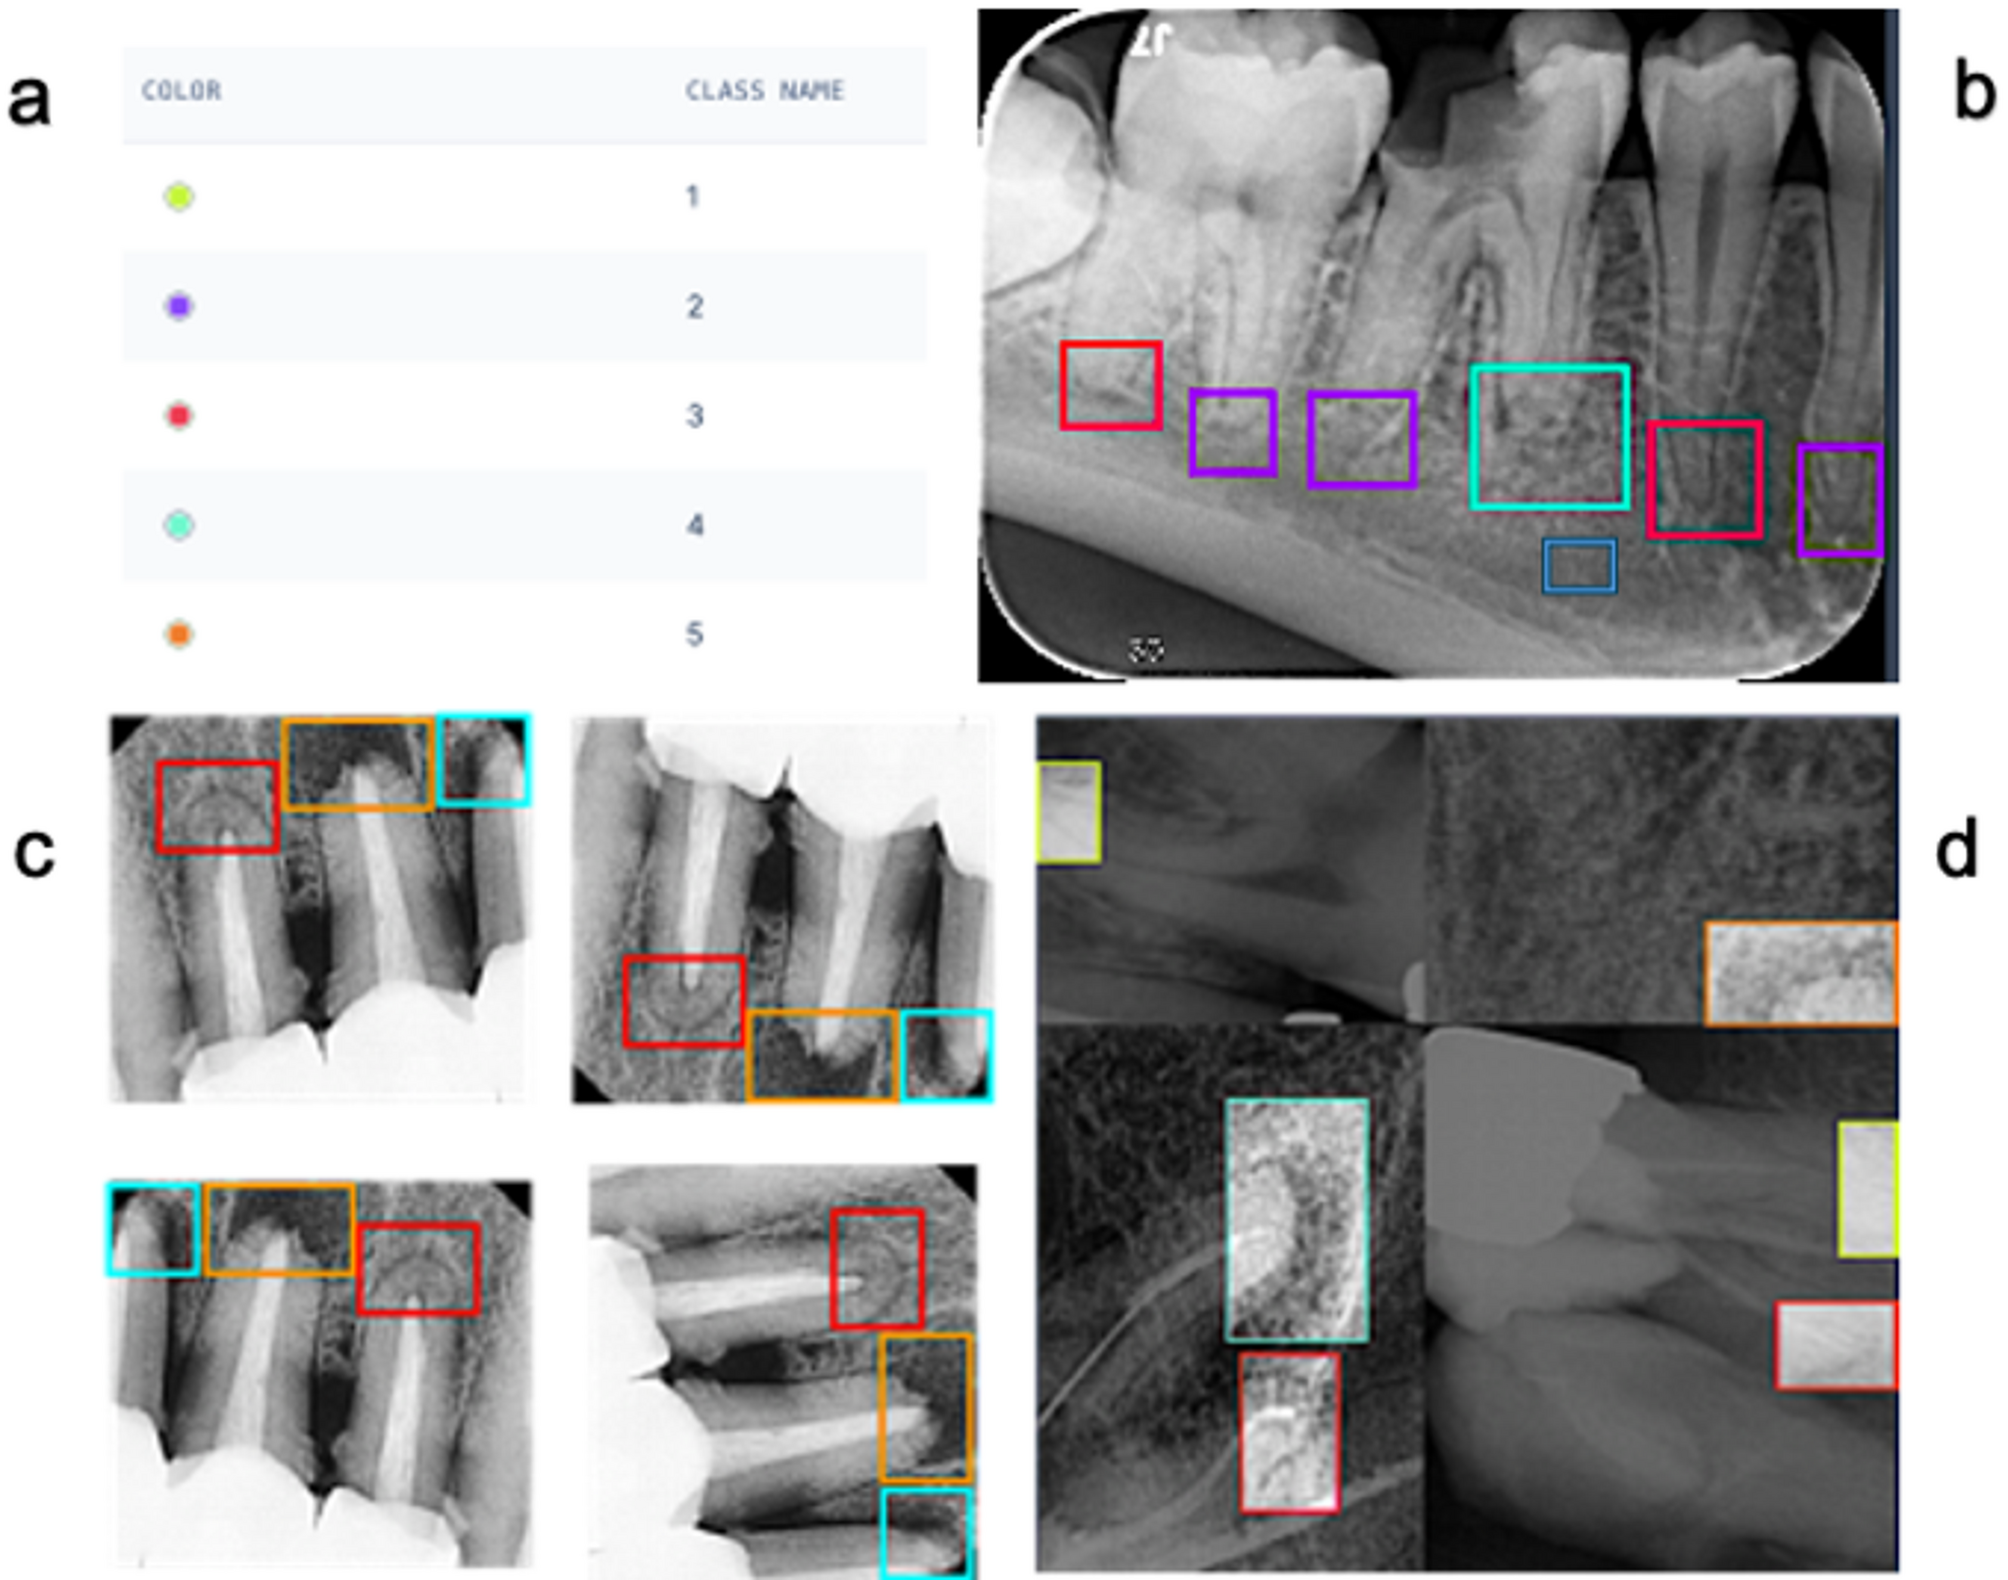

Fig. 1

(a) assigned PAI scores, (b) manual annotation on Roboflow using the bounding box tool, (c) Geometric augmentation of the training dataset through altering pixel location, (d) Application of the mosaic pattern. Note that the increased brightness of boxes in (d) reflects the visualization overlay and is not an image-intensity augmentation.